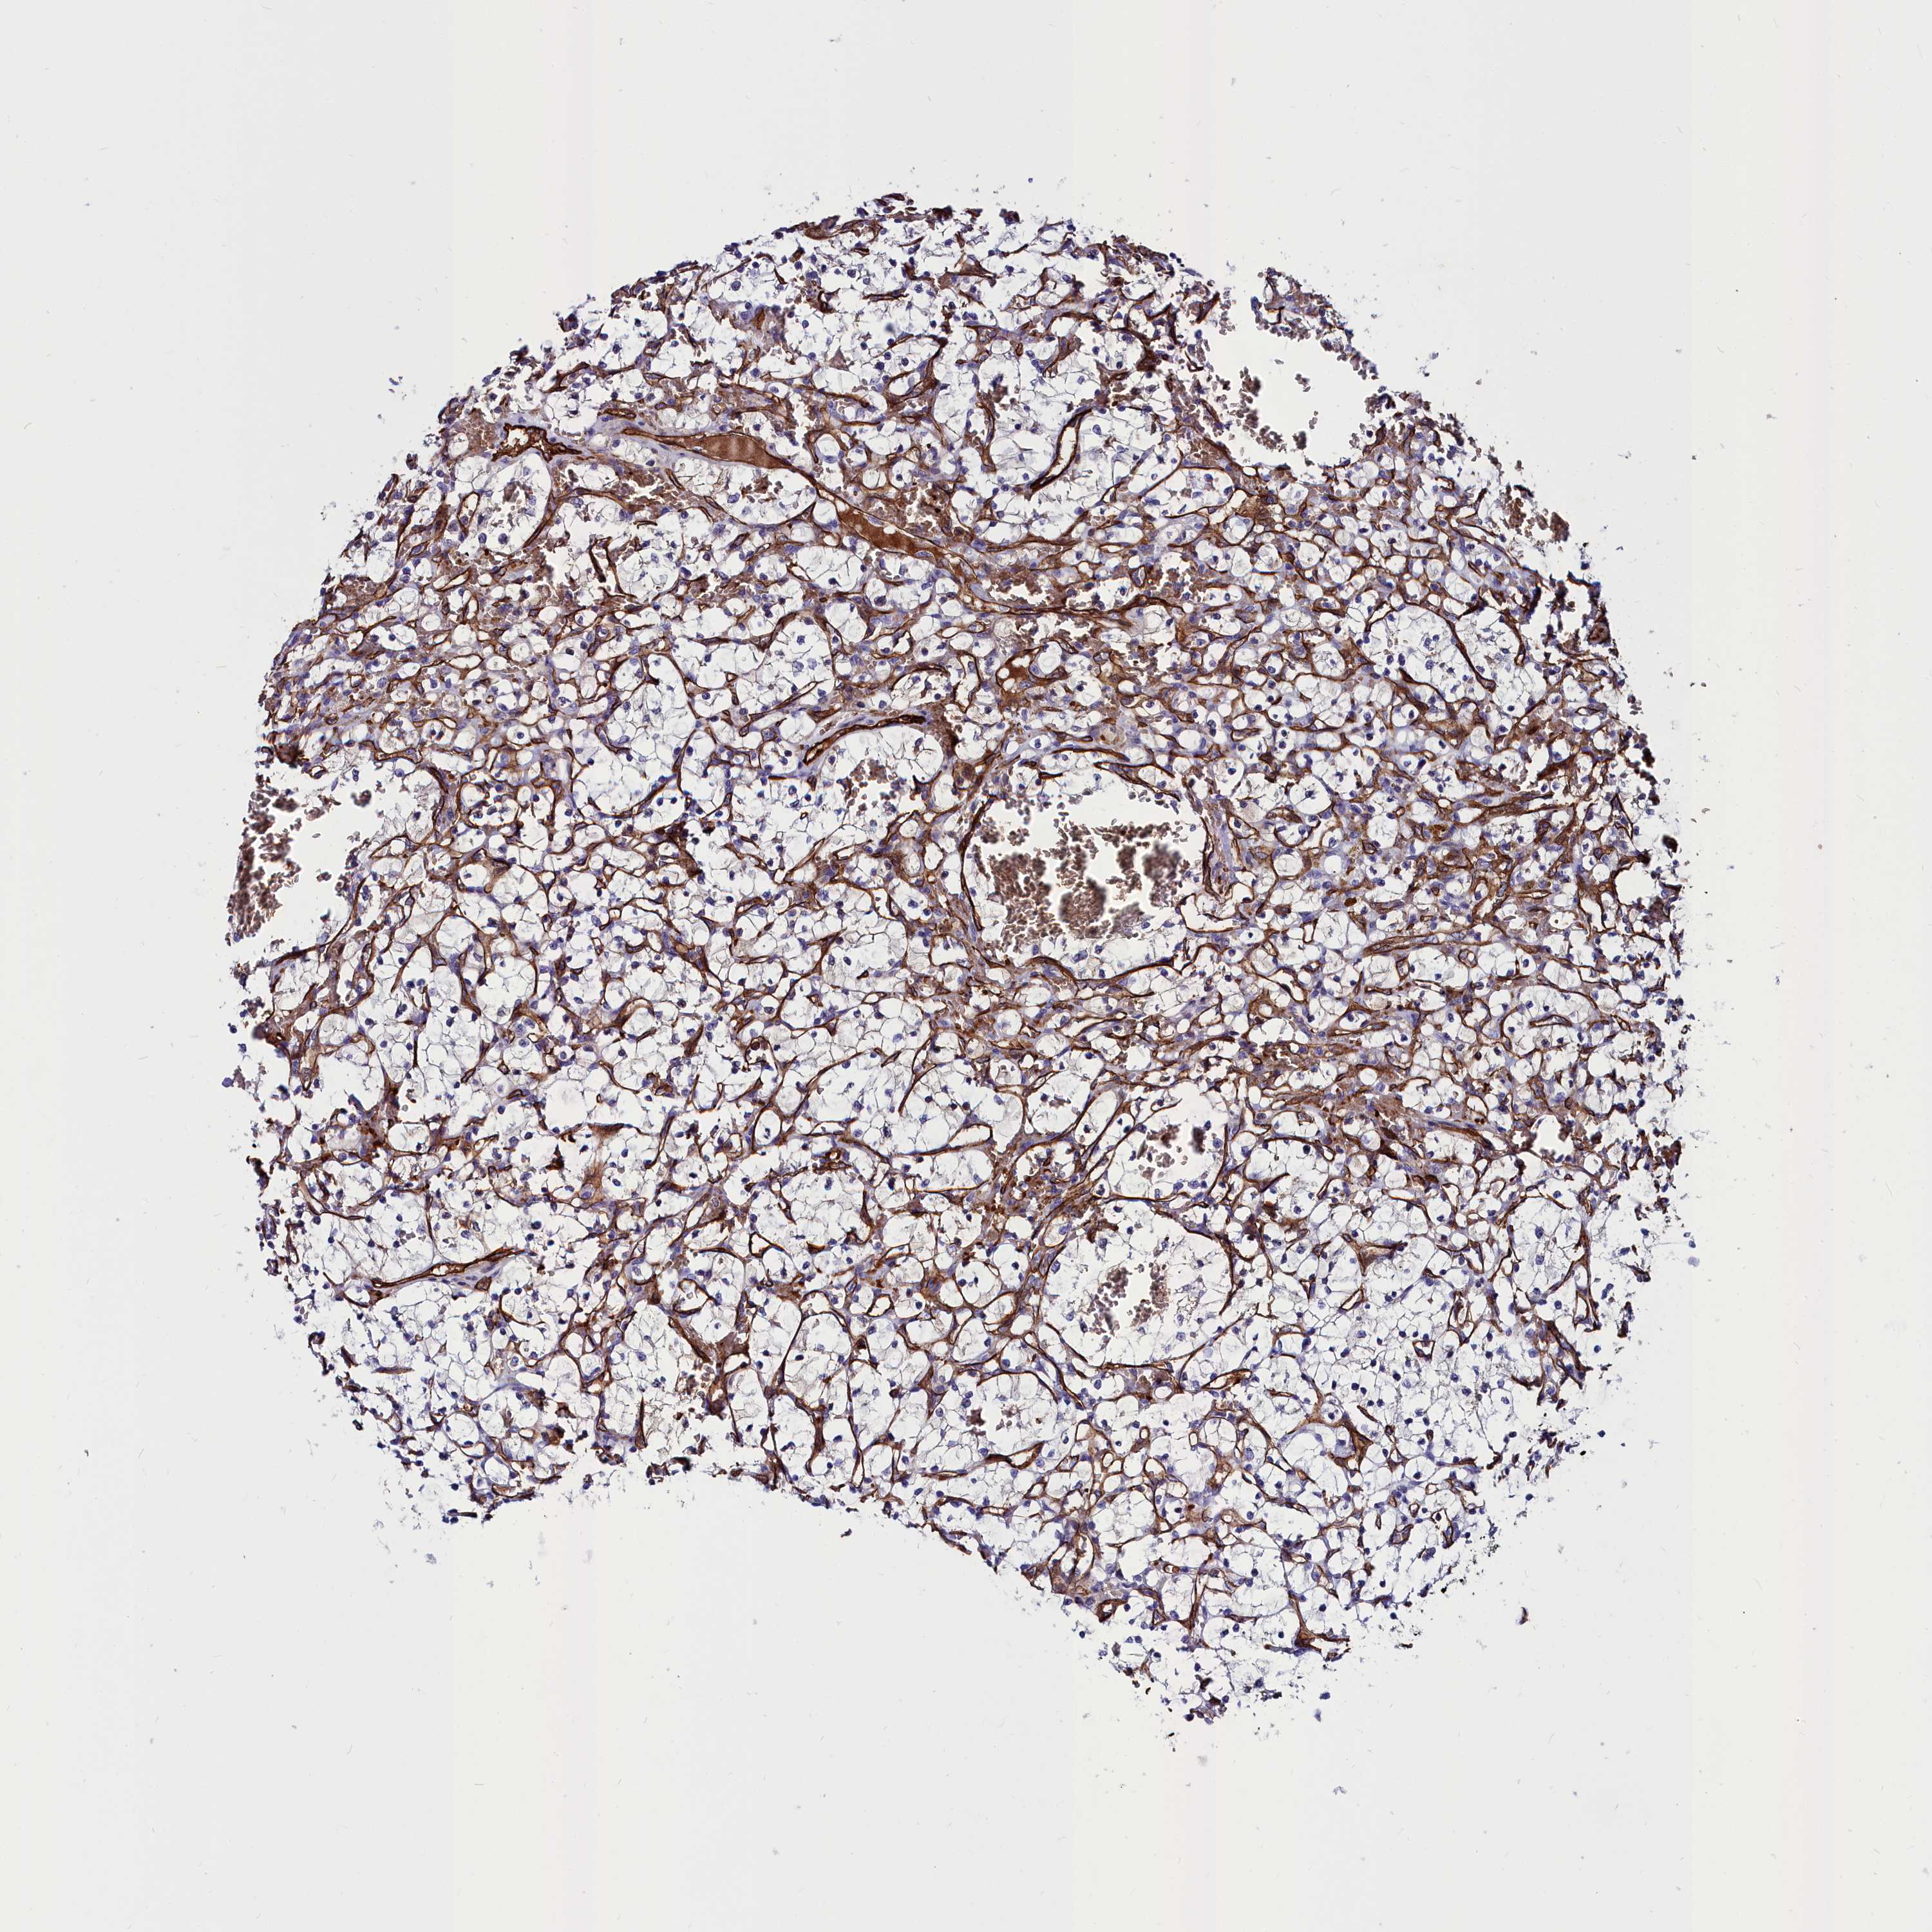

KIDNEY RENAL CLEAR CELL CARCINOMA (VALIDATION) - Interactive survival scatter ploti

The Survival Scatter plot shows the clinical status (i.e. dead or alive) for all individuals in the patient cohort, based on the same data that underlies the corresponding Kaplan-Meier plots. Patients that are alive at last time for follow-up are shown in blue and patients who have died during the study are shown in red.

The x-axis shows the expression levels (FPKM) of the investigated gene in the tumor tissue at the time of diagnosis. The y-axis shows the follow-up time after diagnosis (years). Both axes are complimented with kernel density curves demonstrating the data density over the axes. The top density plot shows the expression levels (FPKM) distribution among dead (red) and alive patients (blue). The right density plot shows the data density of the survived years of dead patients with high and low expression levels respectively, stratified using the cutoff indicated by the vertical dashed line through the Survival Scatter plot. This cutoff is automatically defined based on the FPKM cutoff that minimizes the p-score. The cutoff can be changed by dragging the vertical line or by entering a cutoff value in the square labeled "Current cut-off".

Under the Survival Scatter plot the p-score landscape (black curve; left axis) is shown together with dead median separation (red curve; right axis). Dead median separation is the difference in median mRNA expression between patients who have died with high and low expression, respectively. It is calculated as follows: median FPKM expression of dead patients with high expression - median FPKM expression of dead patients with low expression. This is intended to aid the user in visually exploring custom cutoffs and the associated p-scores and dead median separation.

Individual patient data is displayed and can be filtered by clicking on one or more of the category buttons on the top of the page. Categories describing expression level and patient information include: high, low, alive, dead, female, male and tumor stages. The scale of the x-axis can be toggled between linear and log-scale by clicking on the "x log" button. Mouse-over function shows TCGA ID, patient information and mRNA expression (FPKM) for each patient.

& Survival analysisi

Kaplan-Meier plots summarize results from analysis of correlation between mRNA expression level and patient survival. Patients were divided based on level of expression into one of the two groups "low" (under cut off) or "high" (over cut off). X-axis shows time for survival (years) and y-axis shows the probability of survival, where 1.0 corresponds to 100 percent.

CYP4F11 is not prognostic in Kidney Renal Clear Cell Carcinoma (validation)

Best expression cut offi

Based on the FPKM value of each gene, patients were classified into two groups and association between prognosis (survival) and gene expression (FPKM) was examined. The best expression cut-off refers the FPKM value that yields maximal difference with regard to survival between the two groups at the lowest log-rank P-value. Best expression cut-off was selected based on survival analysis .

When clicking on this number, the vertical dashed line indicating cut-off, the interactive survival plot, and the Kaplan-Meier curve will be adjusted to show results based on the best expression cut-off.

: 3

P scorei

Log-rank P value for Kaplan-Meier plot showing results from analysis of correlation between mRNA expression level and patient survival.

N/A

TCGA RNA samplesi

RNA-seq data is reported as average FPKM (number Fragments Per Kilobase of exon per Million reads), generated by the The Cancer Genome Atlas (TCGA) .

Normal distribution across the dataset is visualized with box plots, shown as median and 25th and 75th percentiles. Points are displayed as outliers if they are above or below 1.5 times the interquartile range. FPKM values of the individual samples are presented next to the box plot.

Average pTPM 6.0

Number of samples 100